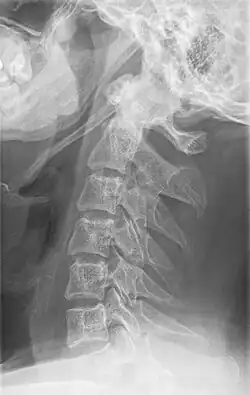

Die Diagnose kann bei klinischem Verdacht mittels Röntgen-Aufnahmen in der Regel als Blickdiagnose im Orthopantomogramm erkennbar, oder mit der Computertomographie gestellt werden. Die Sonographie und die Magnetresonanztomographie sind weniger geeignete Methoden.